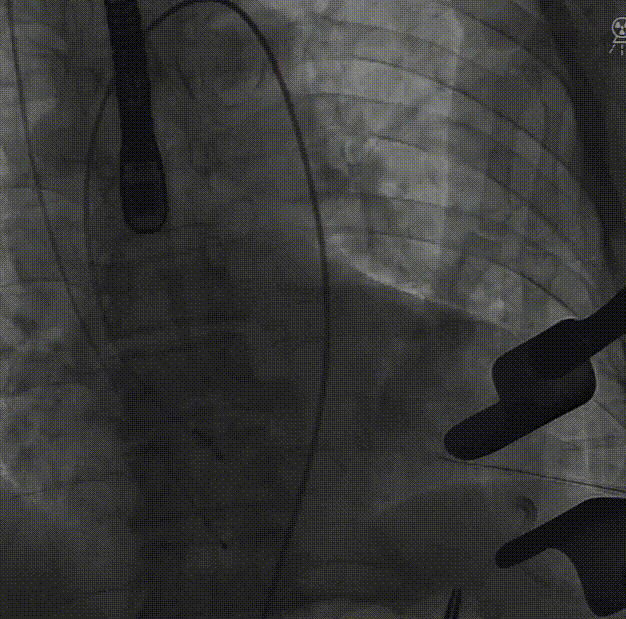

穿刺心尖,导丝跨瓣:

主动脉根部造影: